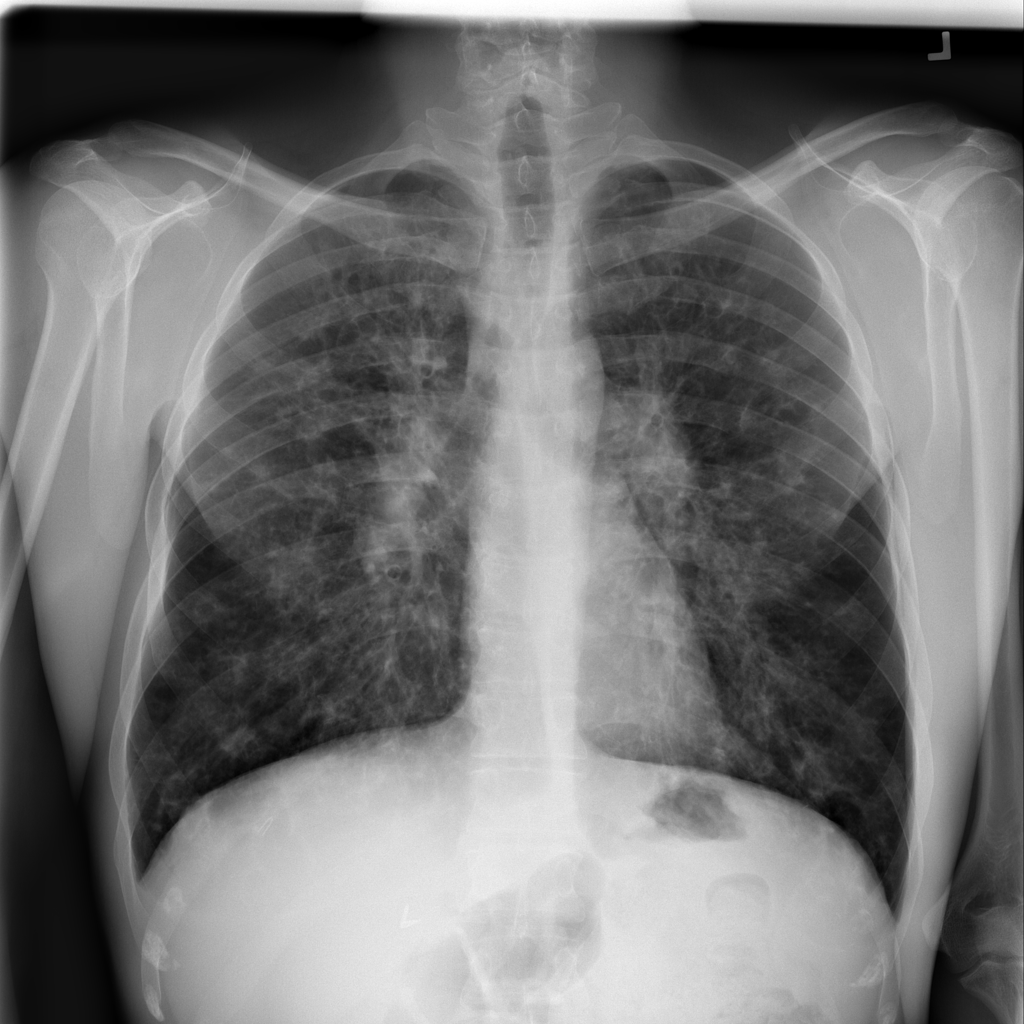

PAT-E066 · IMG-010Fibrosis

PAT-E066 · IMG-010

PA